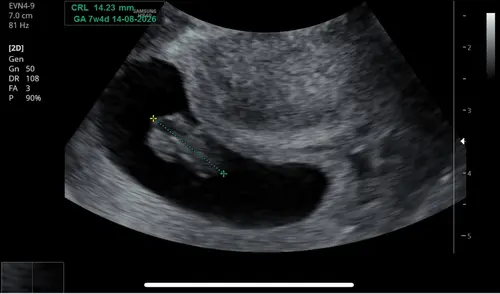

Zo leuk om dit allemaal te zien! Vorige week al een echo gehad toen dachten ze net 5 weken amper 4 mm wel kloppend hartje te zien. Vandaag extra ivm bloedverlies en al 1,4 cm🤩 en een snel en goed kloppend hartje. 7+4 volgens deze meting. Volgende week woensdag weer een echo 😊.